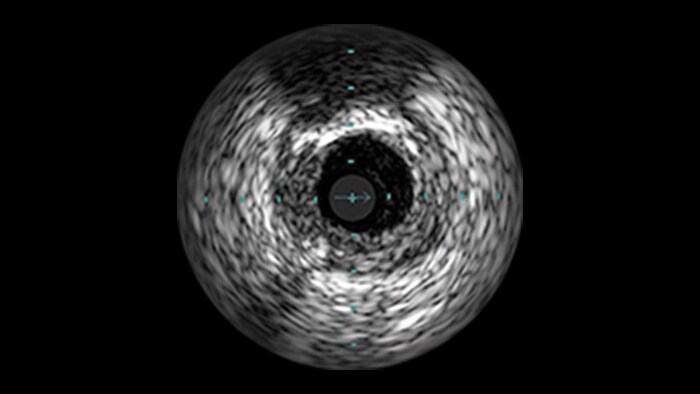

Saphenous vein graft and thrombus lesions

Advanced tools for optimal PCI outcomes